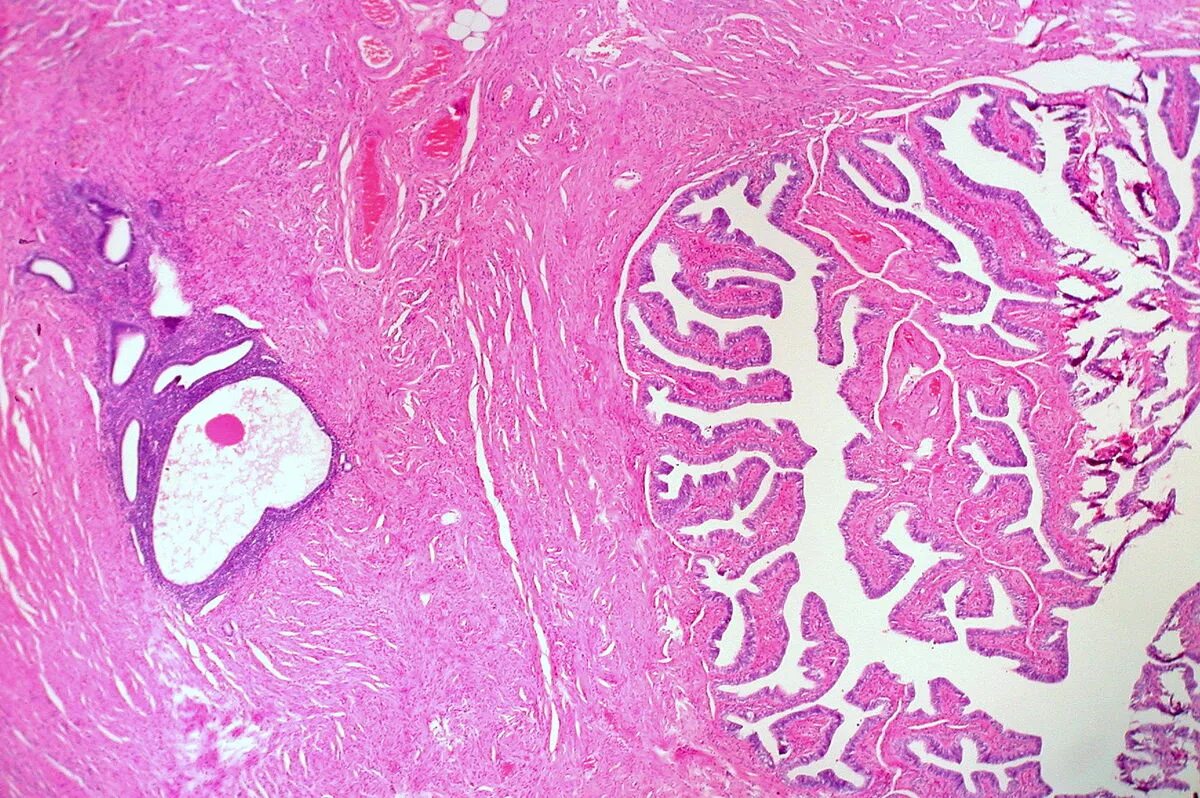

Что показала гистология замершей